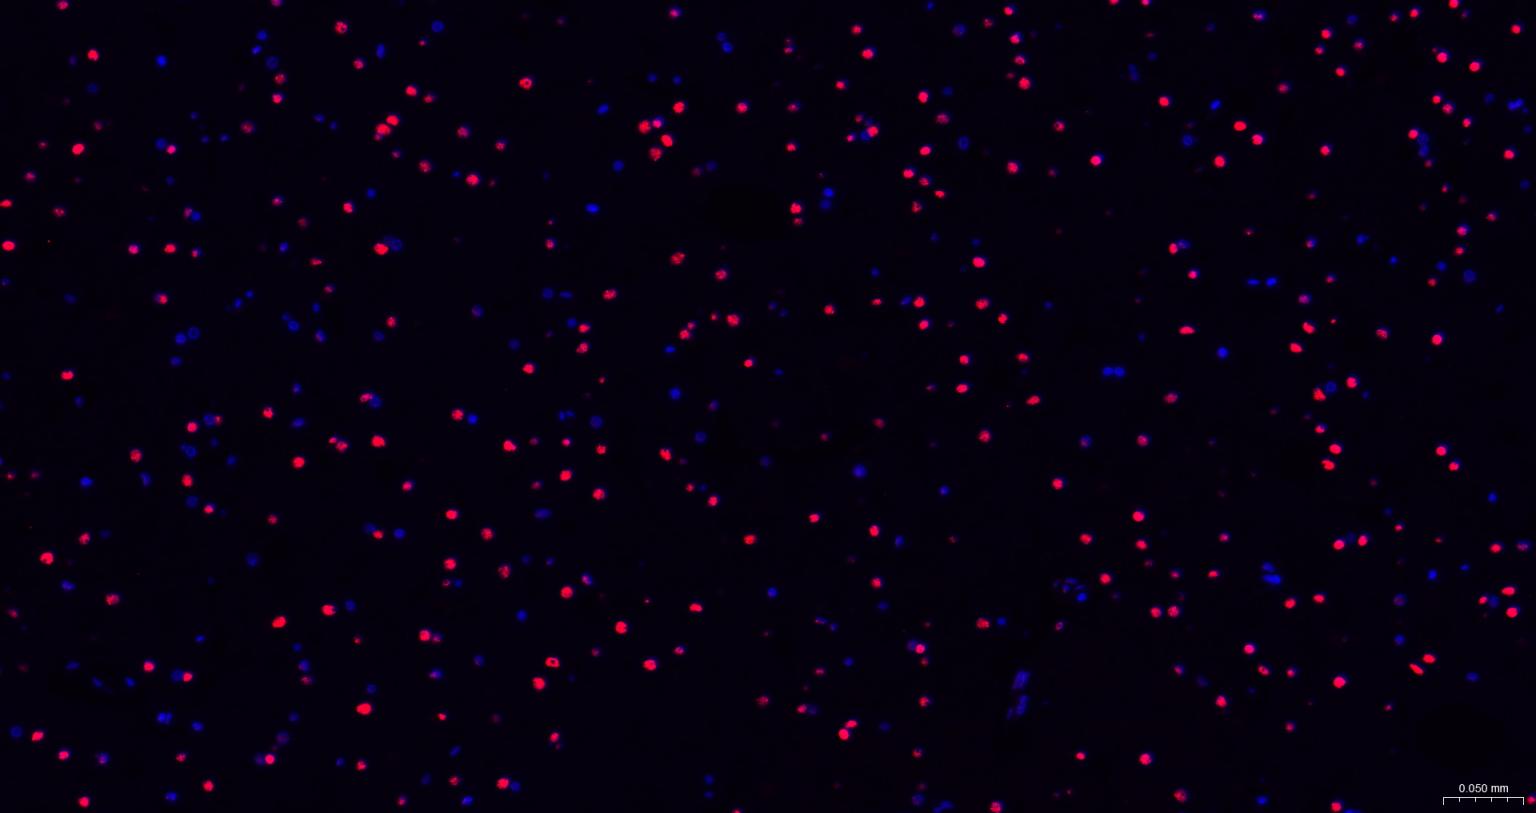

Paraformaldehyde-fixed, paraffin embedded Rat Cerebrum; Antigen retrieval by boiling in sodium citrate buffer (pH6.0) for 15 min; The section was incubated with TARDBP Monoclonal Antibody, Unconjugated (bsm-52949R) at 1:200 overnight at 4°C. Followed by conjugated Goat Anti-Rabbit IgG antibody (Red, bs-0295G-BF594), DAPI (blue, C02-04002) was used to stain the cell nuclei.